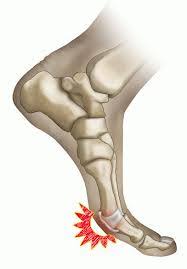

Doctors call this injury turf toe because it appears more often in athletes playing on artificial turf. An athlete who suffers from this condition may complain of pain around the ball of the foot, particularly on the bottom. Turf toe is an injury of the first metatarsophalangeal(mtp) articulation, due to hyperextension of the big toe. What are possible complications of turf toe? Turf toe injury best treatment! This can cause you to sprain or injure your toe and the ligaments that surround it. Even though it is not considered a serious injury it can be very debilitating and take a long time to heal. Turf toe is a common sports injury that occurs when the bones and tissue around the big toe become damaged.

— written by bethany cadman on october 22, 2018. Turf toe is an injury of the first metatarsophalangeal(mtp) articulation, due to hyperextension of the big toe. A common athletic injury from field sports. An athlete who suffers from this condition may complain of pain around the ball of the foot, particularly on the bottom. Turf toe is a sprain of the fibrous joint capsule that supports the metatarsophalangeal (mtp) joint at the base of the big toe. We look at common causes, symptoms & treatment a turf toe injury develops when the big toe is bent too far back into hyperextension, most commonly when front of the foot is fixed to the ground, the. Turf toe is essentially a sprain or hyperextension of the toe. Suspect you have turf toe? It occurred more frequently in american football players after artificial turf became more common on playing fields. Taping will also help protect the ligament when returning to full fitness, especially if the ligament has been overstretched causing joint laxity. An injury where the big toe bends back too far aka metatarsophalangeal joint sprain. There are three grades of turf toe, 1 being the least serious and 3 being the most serious. No matter what grade of toe injury, the joint still.

We look at common causes, symptoms & treatment a turf toe injury develops when the big toe is bent too far back into hyperextension, most commonly when front of the foot is fixed to the ground, the. What are possible complications of turf toe? It happens most often in football players, but it can happen in other sports and activities as well. Turf toe can be mild or severe depending on the injury grade. Turf toe can range from a mild injury with only minor ligament damage to a chronic injury involving inflammation of the joint capsule and progressive cartilage formation and. The name turf toe comes from the fact that this injury is especially common among athletes who play on artificial turf. Learn the causes, symptoms and treatments for this common toe injury. A sprain to the first metatarsophalangeal(mtp) joint , otherwise known as a 'turf toe' or 'death toe' , is a common injury in athletes in which the plantar capsule and the ligament of first metatarsophalangeal joint is damaged. Turf toe is a common sports injury that occurs when the bones and tissue around the big toe become damaged. Doctors call this injury turf toe because it appears more often in athletes playing on artificial turf. Discover what turf toe is at 10faq health and stay better informed to make healthy living decisions. An athlete who suffers from this condition may complain of pain around the ball of the foot, particularly on the bottom. Even though it's linked to artificial surfaces found in most domed stadiums (hence its name), players can get turf toe on grass, as well as any other firm surface.

A physician will typically diagnose turf toe based on an athlete's symptoms, sports history, and a physical examination of the injured toe joint. Even though it's linked to artificial surfaces found in most domed stadiums (hence its name), players can get turf toe on grass, as well as any other firm surface. It is seen at all levels of competition, even among professional athletes. Most athletes suffering from this sports injury will recall exactly when and how the injury happened. Artificial turf is a harder surface than grass and does not have much give when forces are placed on it. It happens most often in football players, but it can happen in other sports and activities as well. A turf toe taping technique will support and protect the toe preventing it from bending in the direction that will stress the ligament causing pain. A sprain to the first metatarsophalangeal(mtp) joint , otherwise known as a 'turf toe' or 'death toe' , is a common injury in athletes in which the plantar capsule and the ligament of first metatarsophalangeal joint is damaged. The term turf toe was first coined by bowers and martin1 in a 1976 article describing capsuloligamentous sprains at the first metatarsophalangeal joint sustained by collegiate football players on artificial turf. Turf toe is a sprain of the main joint of the big toe. What are possible complications of turf toe? Turf toe happens when you bend your big toe up toward the top of your foot too far. A turf toe injury can damage any part of the plantar complex, causing mild to more severe injuries.